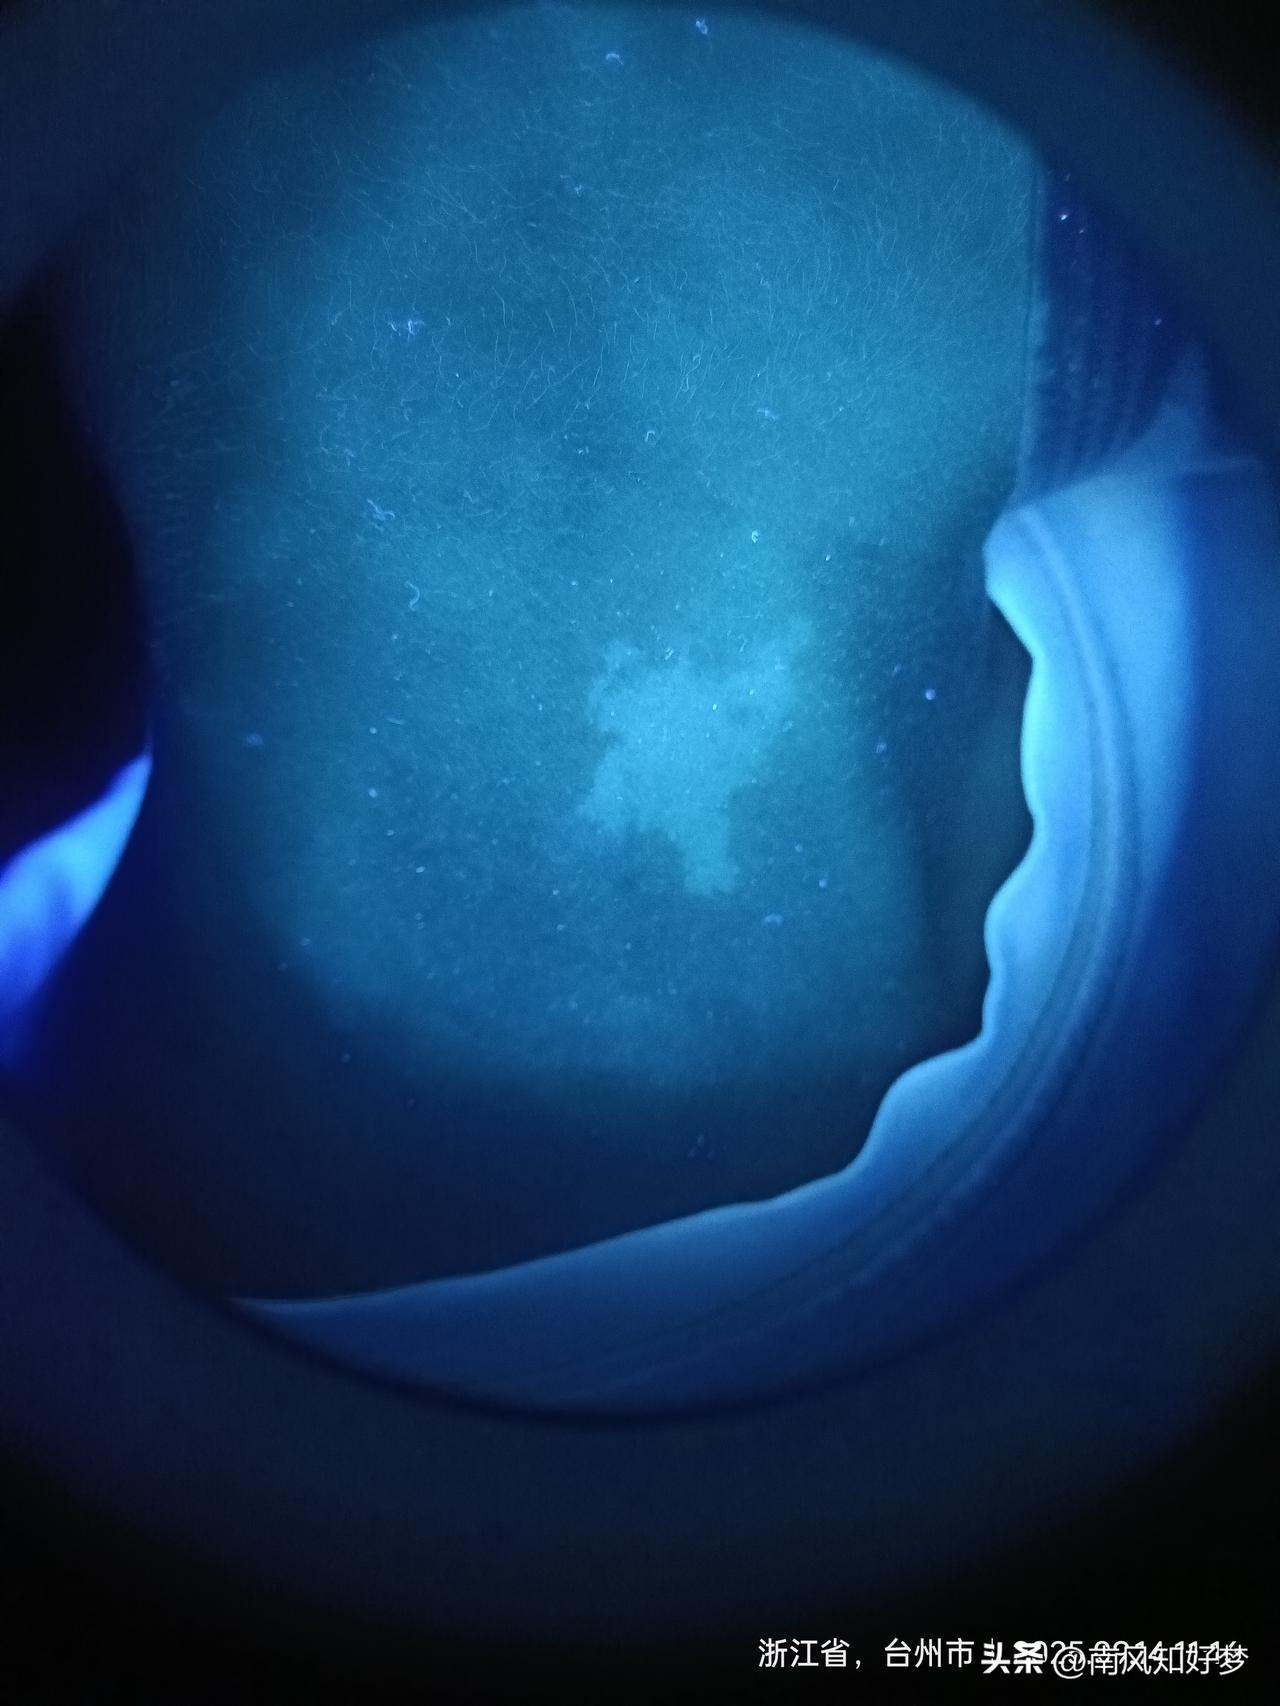

脖子上一块紫外灯照,说无色质,没有什么药,就检查[流泪]